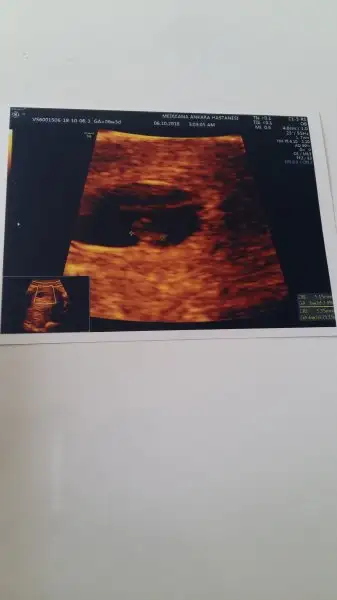

Aynen cok yeni gebeligin tahminim 3haftalik gebeliksin. 2hafta sonra 5.hafta olur kese gorulebilir. Yemene icmene dikkt et gerisini bebisin halleder :))

Şimdi şöyle burdaki hastane hep tanıdık bizim o yüzden ben aldım ama verirler mi bilmiyorum rica edersen alabilirsin bence ya benimle dalga geçmişti hoca bebek yok ki kese var alsan napcan diye ama vermişti yinede sende bi işte bakalım :)